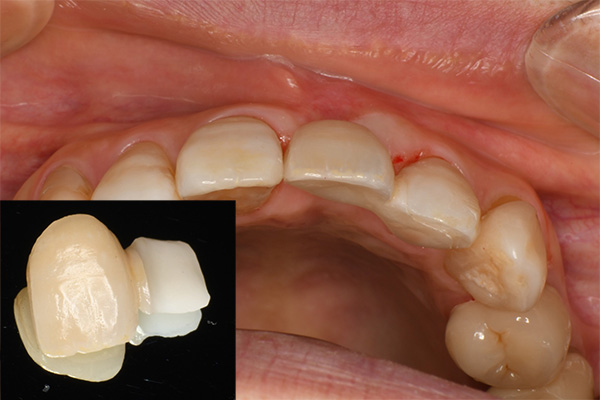

左隣りの歯の裏側を削る切削量は最小限

装着時、歯肉は左右対称に近い感じになる